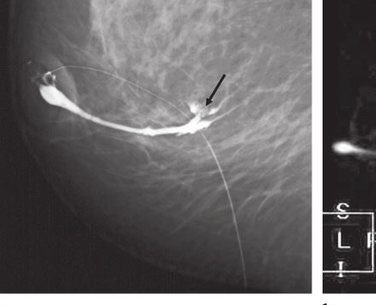

٢-التصوير الشعاعي للثديين

والذي يؤكد على وجود الورم ونوعه الحميد أو المشتبه به ويكون إما بالاشعه الصوتيه للنساء دون ٣٠عاما أو بالماموغرام والصوتيه لل ٣٠عاما وأكبر

8️⃣يميز الفحص الشعاعي بين التكتلات الصلبه والسائلة والتي تدعى بالاكياس وايضا صفاتها التي تشير الى كتلة حميده غير مقلقة أو الى كتلة فيها اشتباه تستدعي إجراء الخزعة

٣- تتم الخزعة بأخذ عينة من نسيج الكتله الصلبه أو شفط لمحتوى الكيسة بأبره وارسالها للمختبر للتأكد من التشخيص